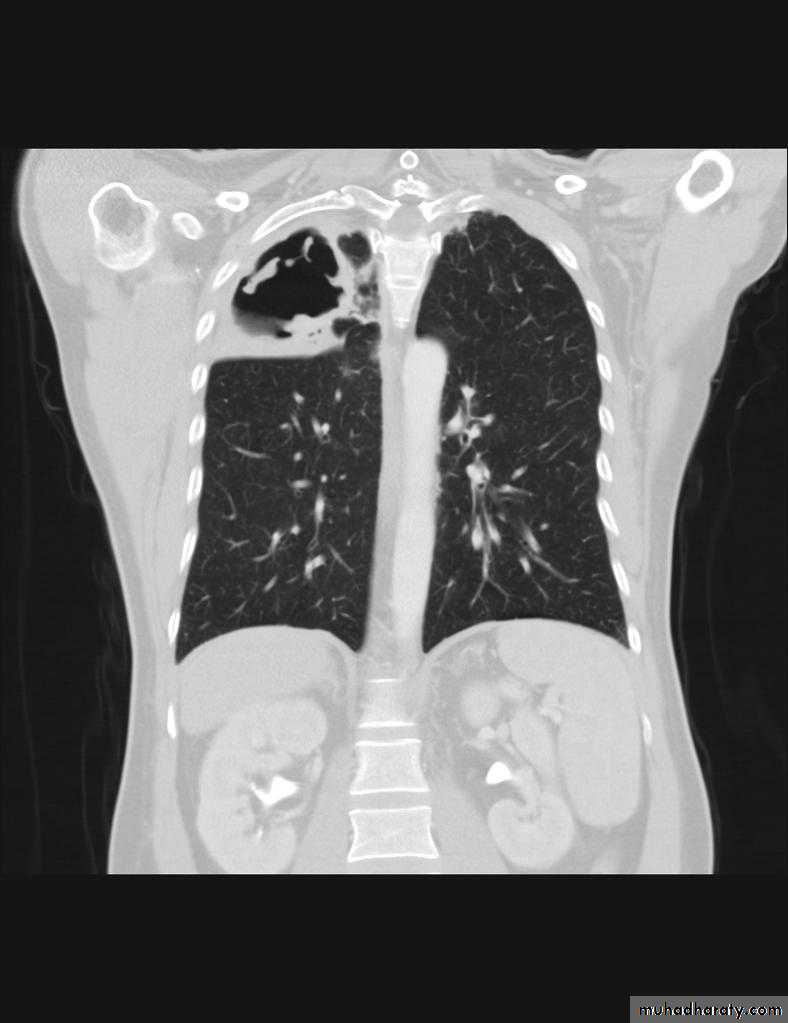

Post-primary pulmonary tuberculosis, also known as reactivation tuberculosis or secondary tuberculosis occurs years later, frequently in the setting of a decreased immune status. In the majority of cases, post-primary TB within the lungs develops in either :

* posterior segments of the upper lobes

*superior segments of the lower lobes

Typical appearance of post-primary TB

1.patchy consolidation or poorly defined linear and nodular opacities in both apices , upper zone in one lung , & lower zone in other lung ( ulternating lesion ) .2. Post-primary infections are far more likely to cavitate with multiple abscess formation & air fluid level more develop in the posterior segments of the upper lobes.

3. Tuberculomas seen in post-primary TB and appear as a well defined rounded mass typically located in the upper lobes .